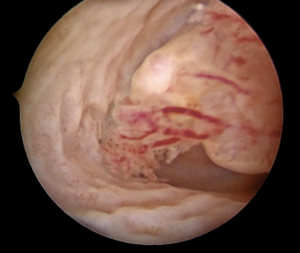

Vaginal assessment and direct visualization are essential for diagnosing patients exhibiting genital bleeding or persistent pathological discharge (See image 3). While small “virginal” specula are available, they can cause discomfort and convey negative psycho-sexual effects on girls and adolescents. Vaginoscopy offers a superior method for assessing intravaginal pathology and diagnosing intravaginal foreign bodies. It is best performed with a hysteroscope equipped with a working channel, such as the Bettocchi set, facilitating diagnosis confirmation and treatment, as seen in our patient.

Image 3

With a caliber of less than 5mm, the procedure is performed gently without the need for specula or blades. Using saline or distilled water for distention provides clear visibility even in cases of scant active bleeding or vaginal discharge, allowing comprehensive visualization of the vaginal canal, cervical integrity, and exploration of the endocervical canal if necessary.